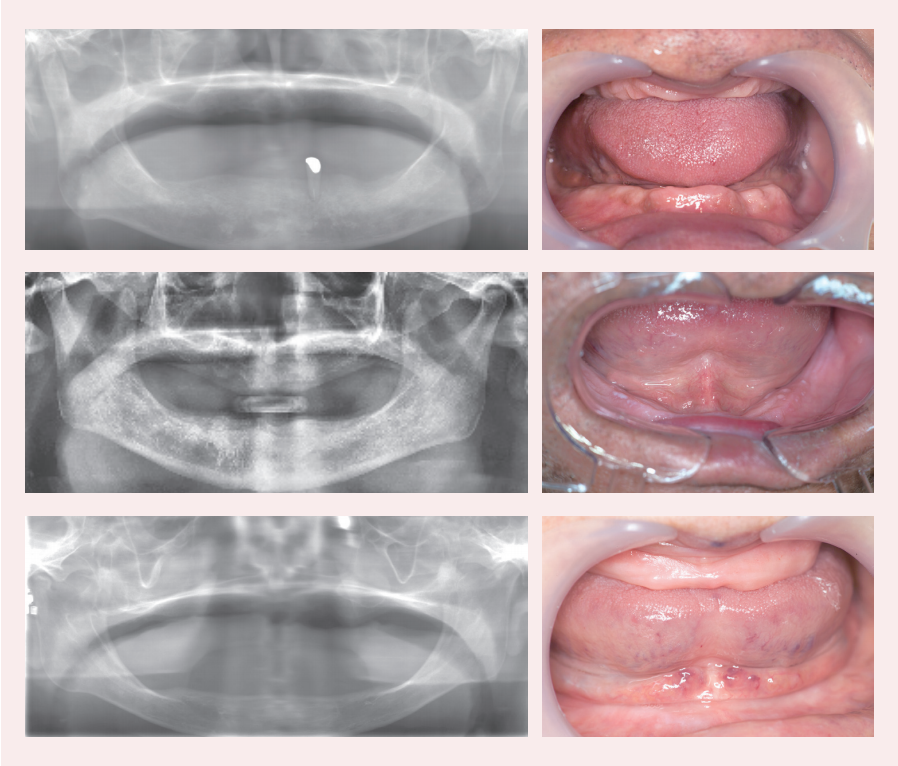

2) 안모와 방사선 검사

상악 치조제는 무치악 상태가 오래되어 치조골흡수가 많다.

하악 치조정은 수평적 치조골흡수가 많다.

3) 구강 내 검사

(1)상악

악제 크기가 작고 치조골흡수가 많이 진행되었다.특히 후방 구치부 부위에 잔존치조제 크기가 너무 빈약하다.

(2)하악

틀니 유지에 필수적인 치조제와 retromolar pad가 빈약하다.